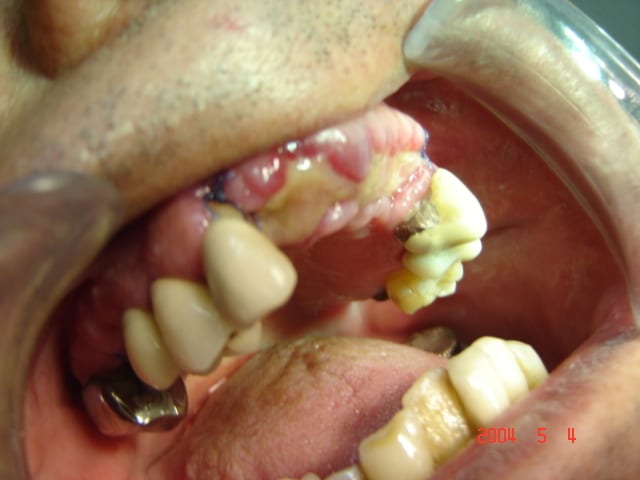

Comme promis , photos du cas a 22 jours post op.

qu'en pensez-vous

12/01/2006 à 13h54

la deuxieme